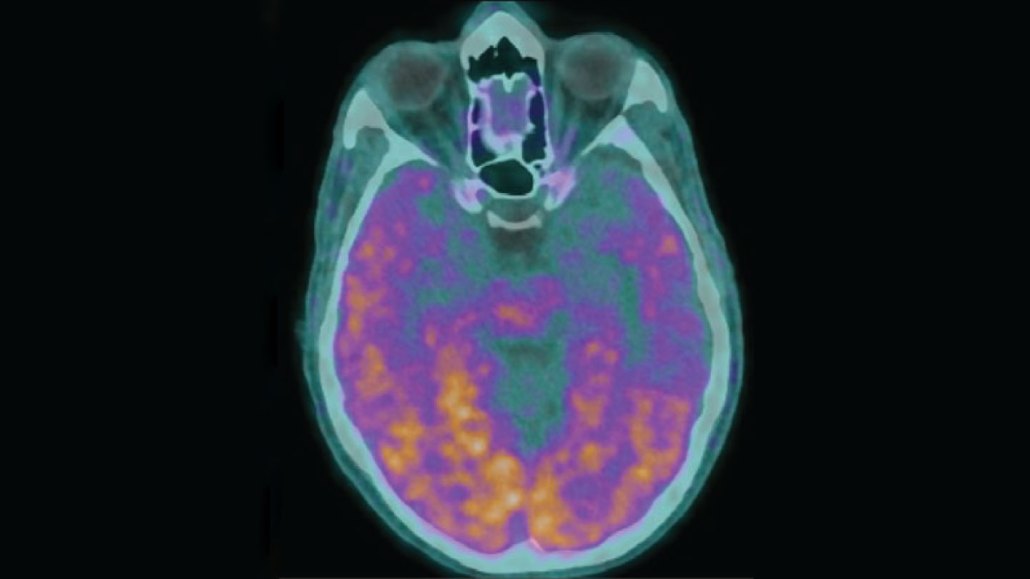

An image of a brain scan with glowing purple and orange spots that mark amyloid-beta.

High levels of the protein amyloid-beta — a hallmark of Alzheimer’s disease — appear orange and purple in this brain scan of a man with the disease. Childhood exposure to the protein via contaminated growth hormone injections may have led the man to develop Alzheimer’s later in life.

G. Banerjee et al/Nature Medicine 2024